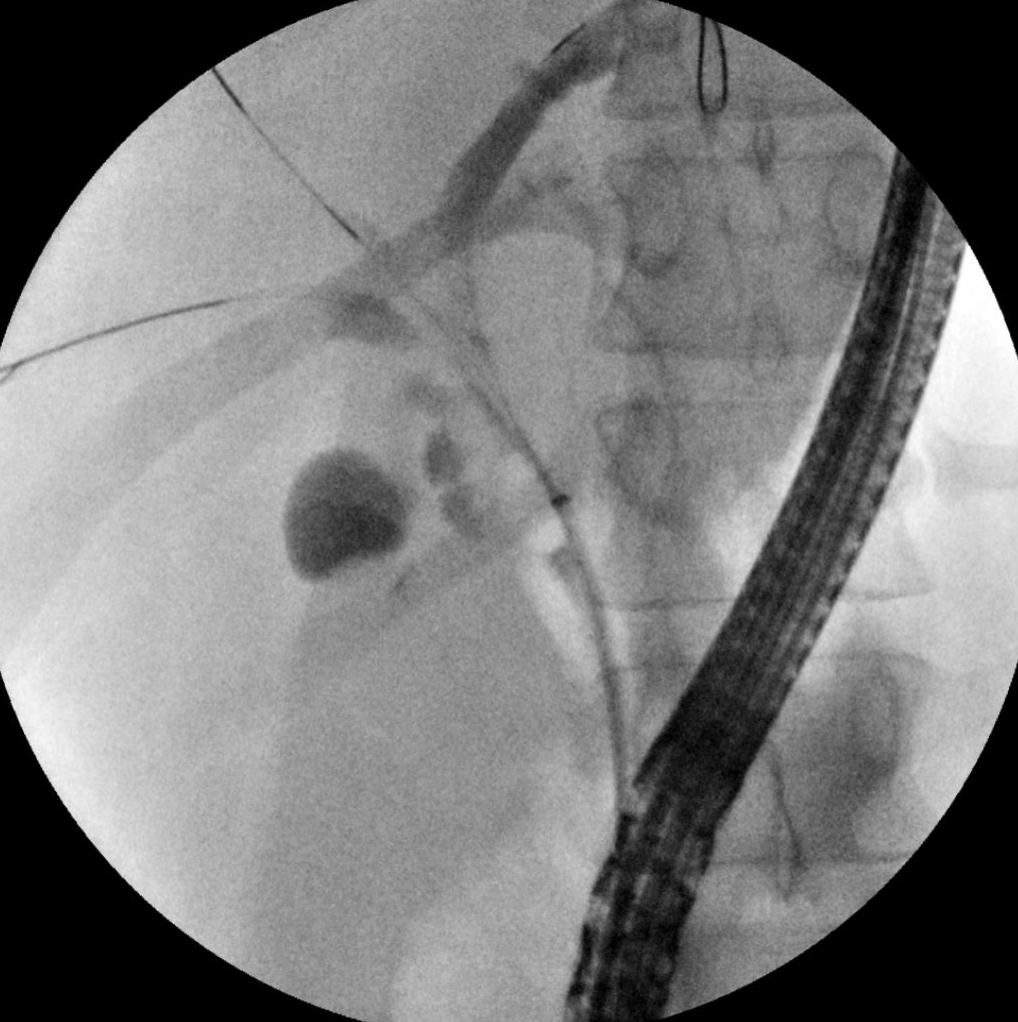

The Interventional Endoscopy team investigates the safety and efficacy of established and novel advanced and interventional endoscopy procedures in children. With a focus on techniques in endoscopic ultrasound (EUS), endoscopic retrograde cholangiopancreatography (ERCP), and other burgeoning endoscopic procedures in pediatric patients, this research serves to assure a safe and optimized approach for less invasive procedures. We actively collaborate with Gastroenterology, Radiology, and Surgery colleagues in sample collection and less invasive endoscopic approaches for multiple disease processes.

- David Vitale (Pancreatitis, Endoscopy, Endoscopic Ultrasound, ERCP)